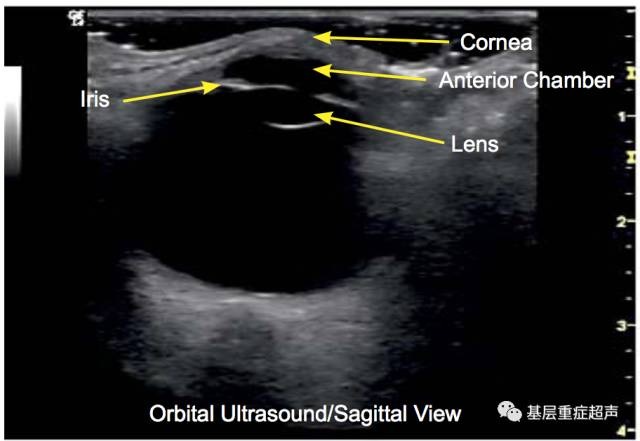

cornea,眼角膜

Lens,晶状体

Anterior Chamber,前房

矢状切面